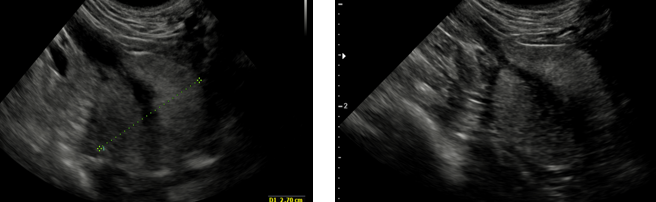

What is being shown here?

R = Dilated renal pelvis

Bottom = dilalted proximal ureter

L = ureters dilated by couple mms —> obstruction of urinary outflow

What is being shown in this bladder?

Cystolith (bladder stone) —> casting acoustic shadow

What is being shown in these bladders?

L —> thickened wall with a hyperechoic lesion arising from the wall —> consistent with a bladder wall mass

R —> thickened and within the lumen we can see hyperechoic areas which may be a mass or could be blood clots.